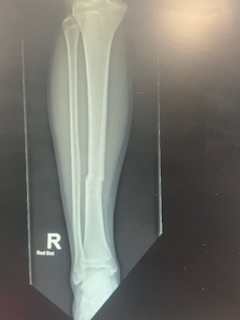

For your viewing pleasure, here are his before and after xrays!

Before:

You don’t need to be a doctor to diagnose the broken bone!